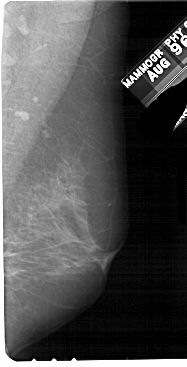

A_1839_1.LEFT_CC

LEFT_CC LINES 5491 PIXELS_PER_LINE 2581 BITS_PER_PIXEL 12 RESOLUTION 43.5 OVERLAY